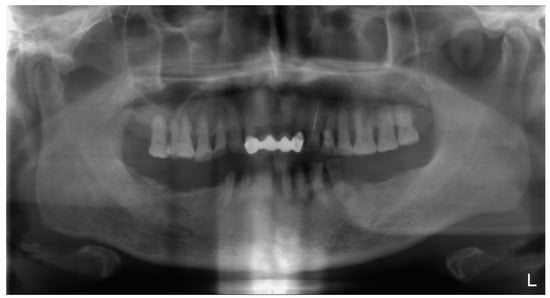

2. Case Description